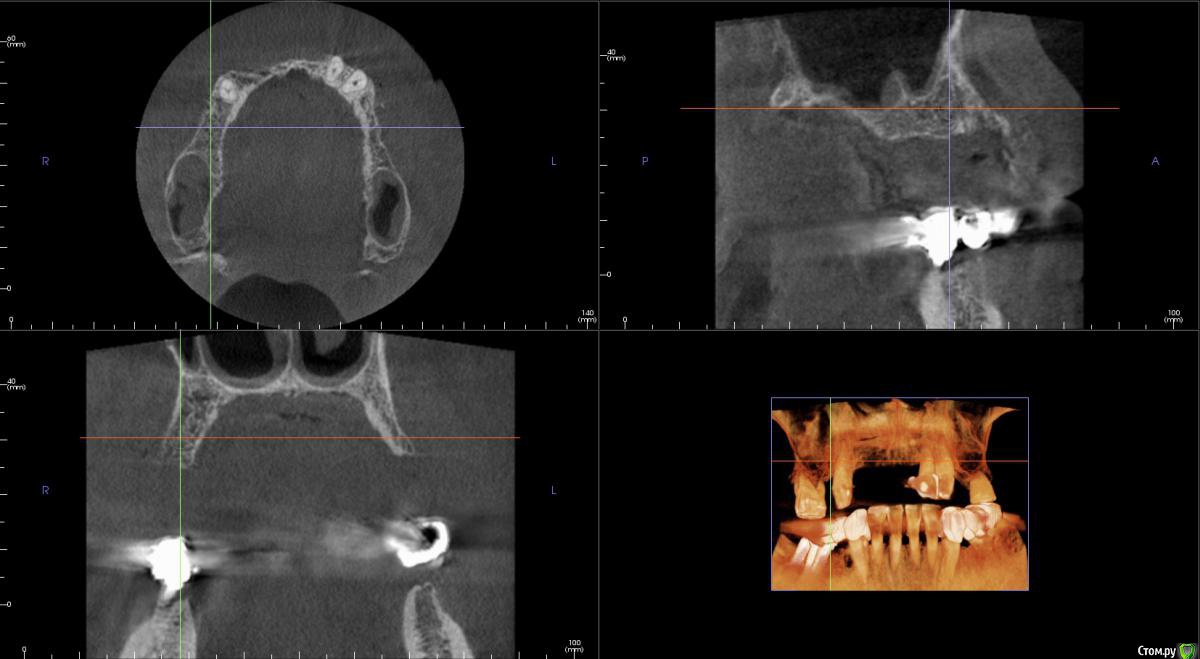

kamranchick Опубликовано 20 сентября, 2016 Поделиться Опубликовано 20 сентября, 2016 Интересует сторона 2. там хочу сделать соссидж, через несколько месяцев сделать закрытый синус и установить 2 винта в области 14 и 16, как вы думаете?и можно ли сделать конструкцию не брав во внимание фронтальный отдел? пациент финансово не тянет фронт Ссылка на комментарий

kamranchick Опубликовано 20 сентября, 2016 Автор Поделиться Опубликовано 20 сентября, 2016 Может убрать всё и на 4 ёх конструкцию предложить?думаю не получится, так как придется аугментировать и фронтальный отдел и боковой отдел чтобы по хорошему сделать все на 4, тем более я работаю на Осстем, а у нас мультиков в системе нет Ссылка на комментарий

колесников Опубликовано 20 сентября, 2016 Поделиться Опубликовано 20 сентября, 2016 думаю не получится, так как придется аугментировать и фронтальный отдел и боковой отдел чтобы по хорошему сделать все на 4, тем более я работаю на Осстем, а у нас мультиков в системе нетНе нужно там ничего аугментировать. Меняете корни на импланты. В обл премоляров так же есть объём по снимку. Иначе череда костных и мягкотканных пластик с неясным прогнозом. Пациент точно не потянет. У остема платформа 4.0 совместима с астровской 4.5-5.0. Можно у астры взять запчасти. Ссылка на комментарий